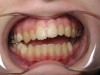

• Orthodontic expansion of the maxillary and mandibular dental arches (Figure 6 and Figure 7).

(6.) Orthodontic dental arch and airway expansion. Images courtesy of Mark Farina, DMD.

Figure 6

(7.) Orthodontic dental arch and airway expansion. Images courtesy of Mark Farina, DMD.

Figure 7